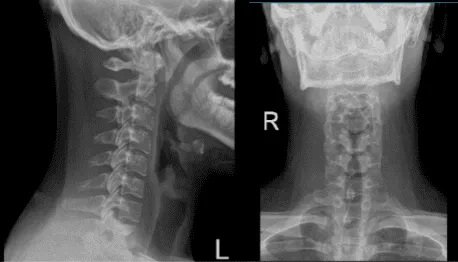

Durante la visita se presentaron radiografías de la columna vertebral y del hombro izquierdo; la radiografía de la columna cervical mostró un enderezamiento anormal de la curva cervical, aunque el hombro izquierdo mostró radiografías normales. En esta revisión, aconsejé al paciente que siguiera tomando ibuprofeno y que se realizará una resonancia magnética la semana siguiente.

Radiografía de la columna cervical 2 vistas